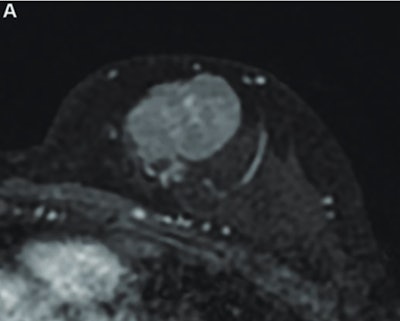

MR image from a 55-year-old patient with triple-negative breast cancer from training set. (A, above) Axial postcontrast T1-weighted image from baseline MRI exam shows unifocal enhancing mass (unifocality: positive). (B, below) Axial postcontrast T1-weighted image from MRI examination per-formed after one cycle of neoadjuvant chemoimmunotherapy shows >37% reduction in lesion size (early tumor shrinkage: positive) and development of non-enhancing region within lesion (percentage enhancement reduction: positive).ARRS